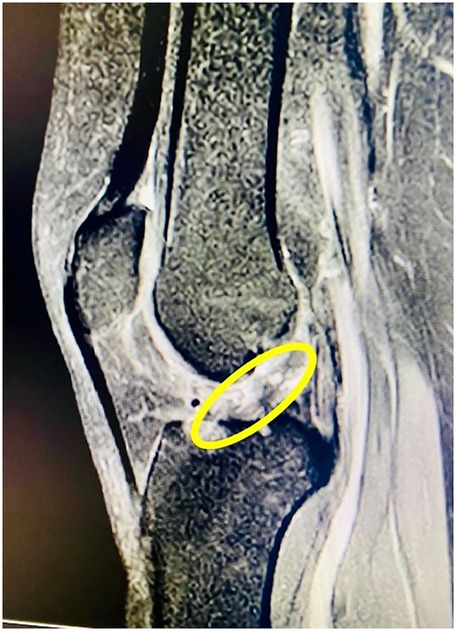

Figure 2

MRI image of a knee joint with a yellow circle highlighting a specific area between the femur and tibia, possibly indicating an abnormality or point of interest.

Figure 2. Post-operative MRI demonstrating successful ACL reconstruction with intact graft alignment.